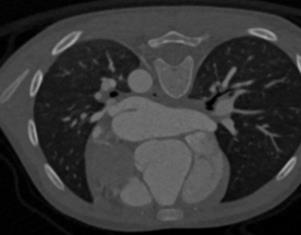

The success of deep learning heavily depends on the availability of large labeled training sets. However, it is hard to get large labeled datasets in medical image domain because of the strict privacy concern and costly labeling efforts. Contrastive learning, an unsupervised learning technique, has been proved powerful in learning image-level representations from unlabeled data. The learned encoder can then be transferred or fine-tuned to improve the performance of downstream tasks with limited labels. A critical step in contrastive learning is the generation of contrastive data pairs, which is relatively simple for natural image classification but quite challenging for medical image segmentation due to the existence of the same tissue or organ across the dataset. As a result, when applied to medical image segmentation, most state-of-the-art contrastive learning frameworks inevitably introduce a lot of false-negative pairs and result in degraded segmentation quality. To address this issue, we propose a novel positional contrastive learning (PCL) framework to generate contrastive data pairs by leveraging the position information in volumetric medical images. Experimental results on CT and MRI datasets demonstrate that the proposed PCL method can substantially improve the segmentation performance compared to existing methods in both semi-supervised setting and transfer learning setting.